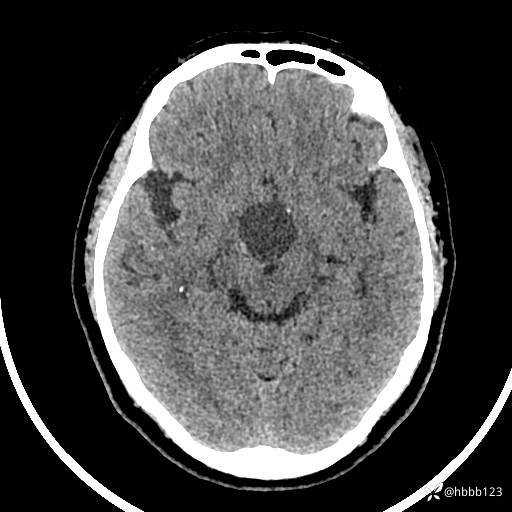

颅脑CT平扫: